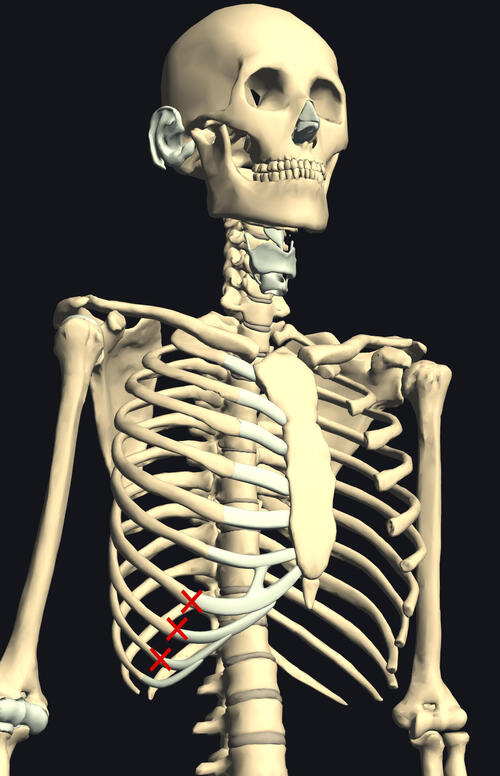

ゴルフスウィングでは第4/5肋骨、咳・クシャミによる損傷部は、

第7~10肋骨側胸部前部が多いです。